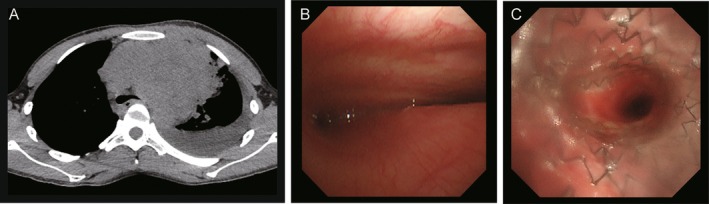

气道支架可以缓解恶性中央气道狭窄的症状,但存在移位的风险,这可能导致支架误食致死。一个22岁的男子接受混合式支架置入气管支气管狭窄的原因是一个未确诊的大纵隔肿块。放置后3周内,在初步诊断为b细胞淋巴瘤的化疗后,支架迁移并被摄入。内镜下成功取出支架。这是首次报道的混合型气管支架摄入病例。对预期肿瘤消退的患者进行早期监测是必要的。

Airway stents provide symptomatic relief in malignant central airway stenosis, but carry the risk of migration, which may result in potentially lethal stent ingestion. A 22-year-old man underwent hybrid stent placement for tracheobronchial stenosis caused by an undiagnosed large mediastinal mass. Within 3 weeks after placement, following initial chemotherapy for provisionally diagnosed B-cell lymphoma, the stent migrated and was ingested. The stent was successfully retrieved endoscopically. This is the first reported case of hybrid tracheal stent ingestion. Early surveillance is warranted in patients with anticipated tumour regression.